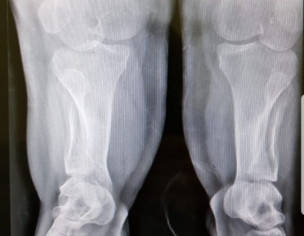

There are some deformities in the bones as seen in the xrays, would want to know about it

Developmental dysplasia of hip bilateral. (DDH). Google it u will know all about it.

there us generalised deformity of all bones and looks shortening as well and Development dysplasia of hip . looks achondroplasic

this is achondroplasia variant of AMC.